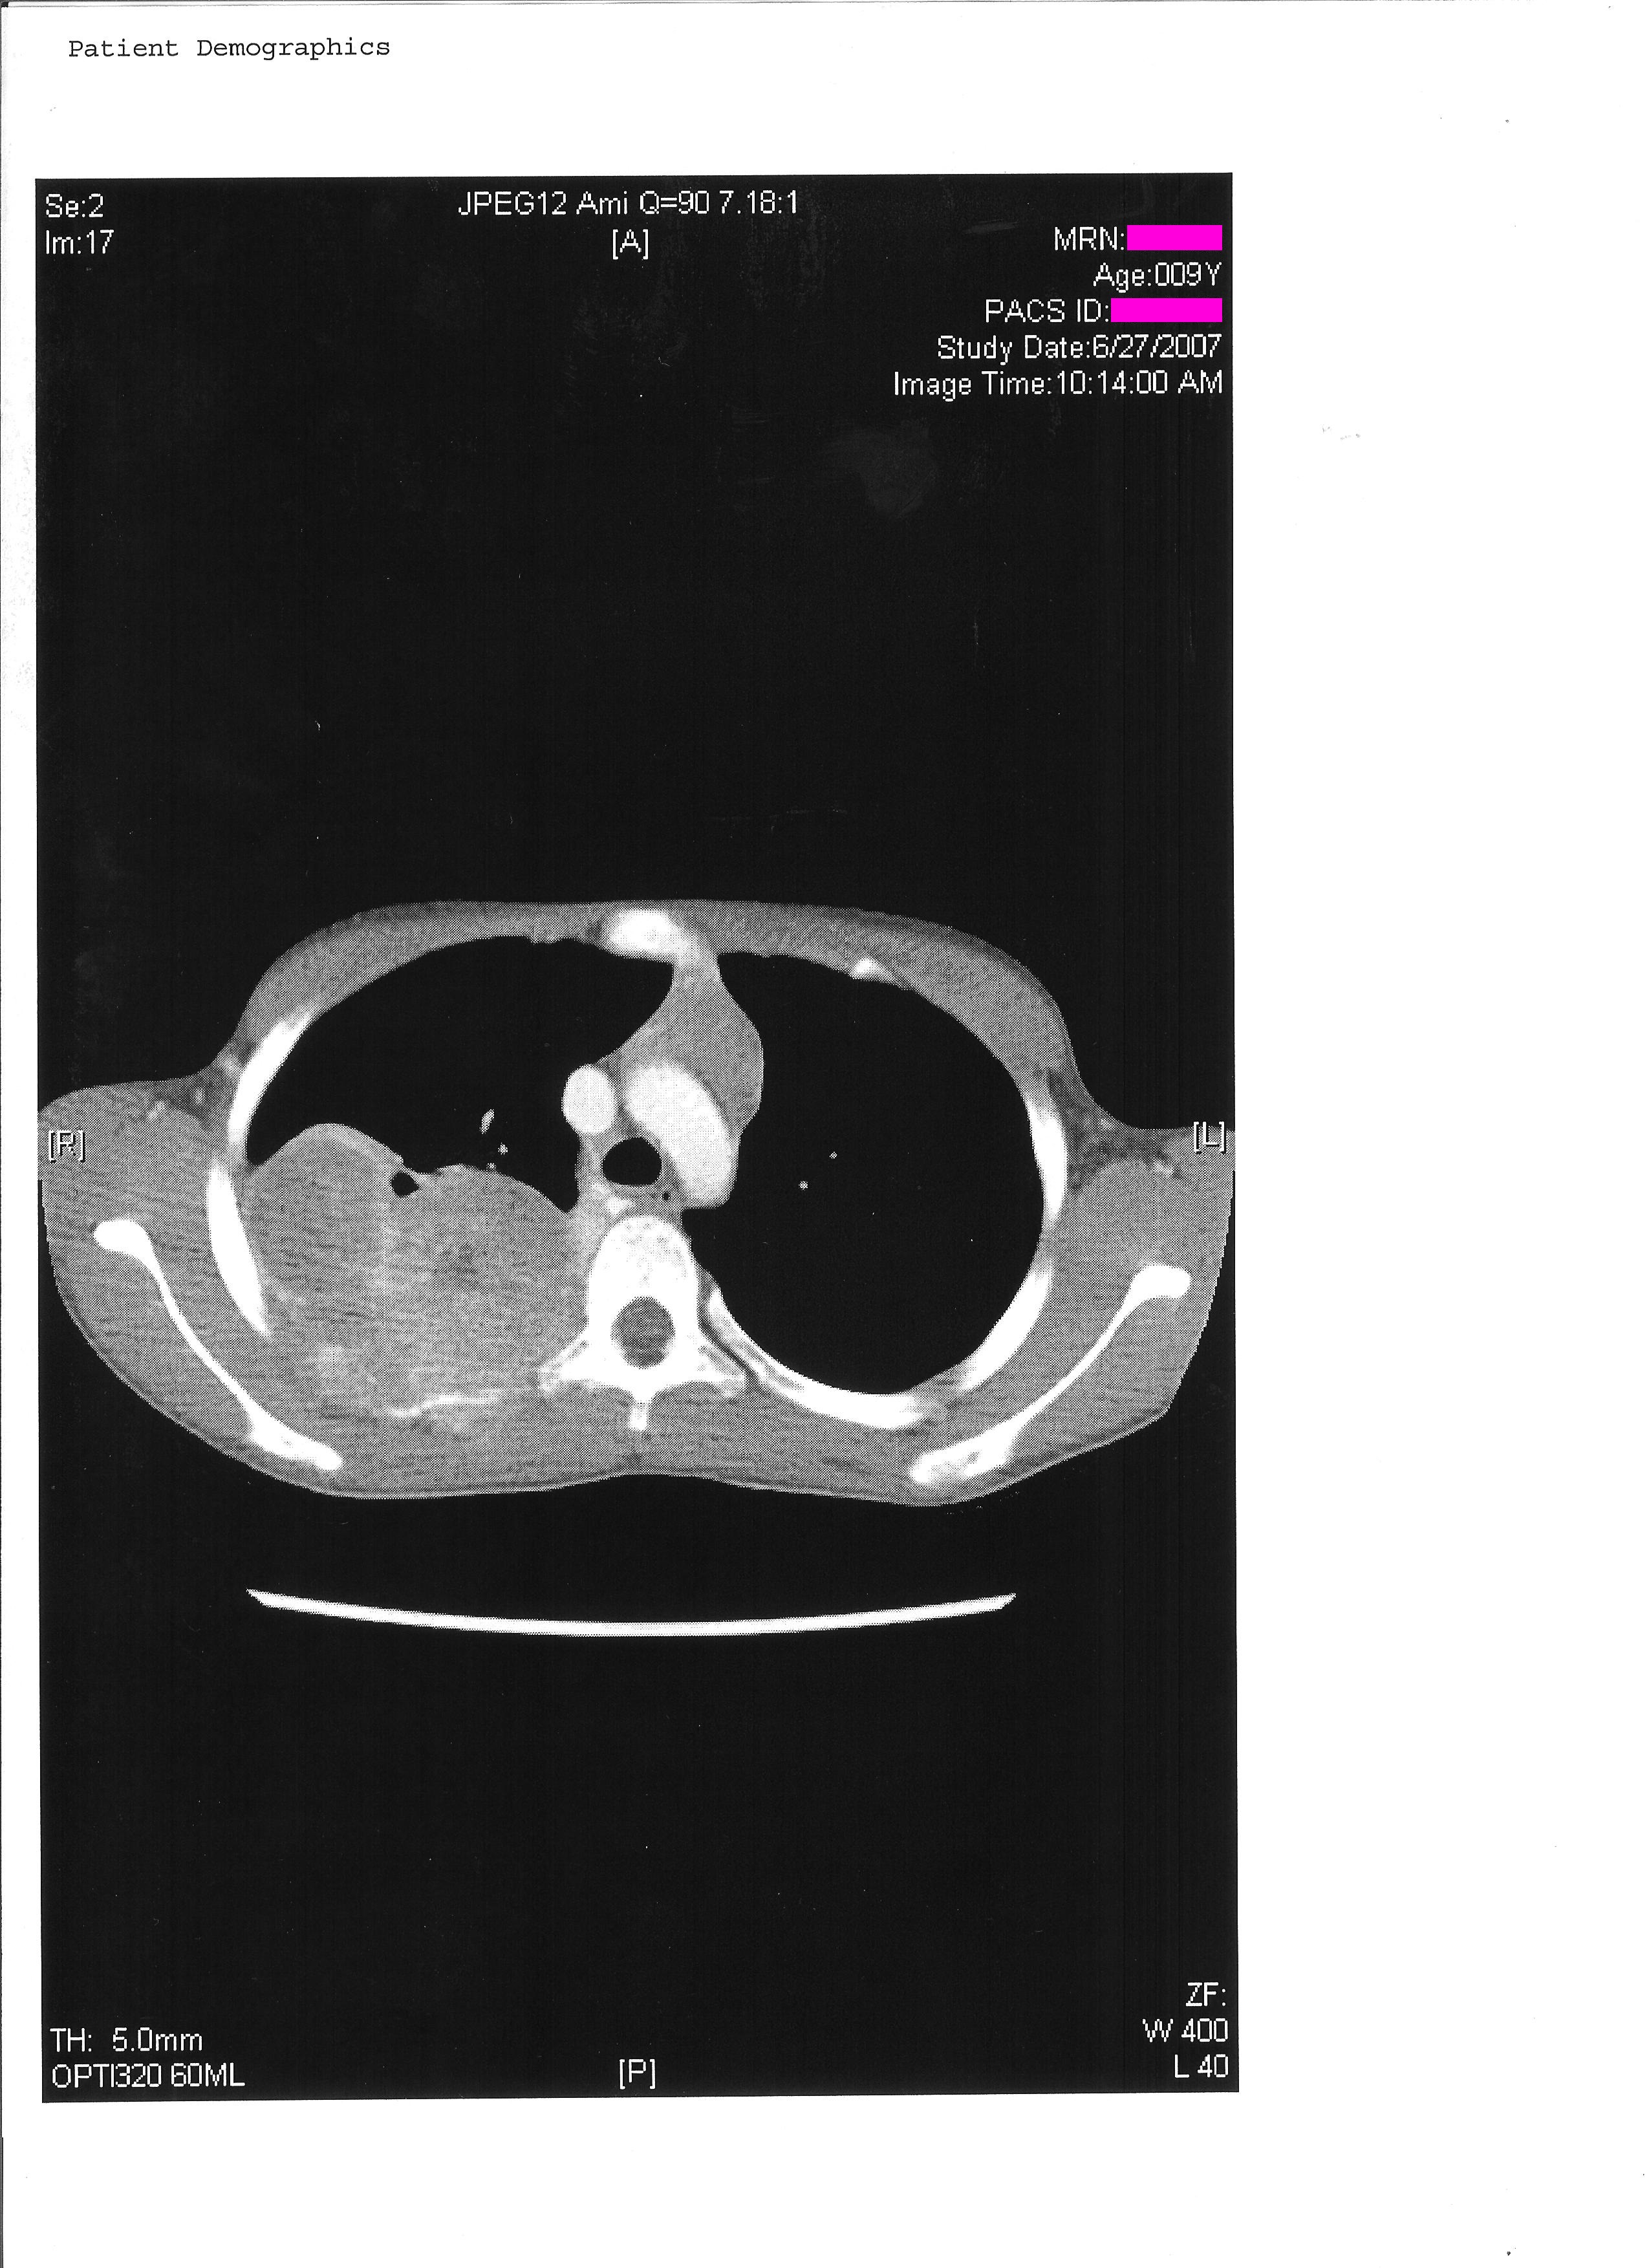

For the next 4 months I was treated with # individual rounds of chemotherapy I was brought in for surgery to remove the tumor. This surgery removed 3 of my ribs, 4-6, from spine to armpit. These were replaced with a VEPTR, Vertical, Expandable, Prosthetic, Titanium, Rib. This prosthetic is clamped onto ribs 3 and 7 spanning the vertical gap. It also has titainum wires wrapped around and inserted into the remaining rib sections to emulate the ribs. Additionally a section of Gortex was added to strengthen the chest wall. Following this surgery I had another # chemotherapy treatments bringing the total up to 14 to total rounds. On March 1st 2008 I finished my last chemo treatment.

My life after treatment has been affected somewhat by physical problems with my prosthetics and generally missing multiple ribs. One of the things I did very quickly was break all of the wires in my back. Some of these segments were removed due to them painfully poking me. They have since stopped using wires with this style of reconstruction.